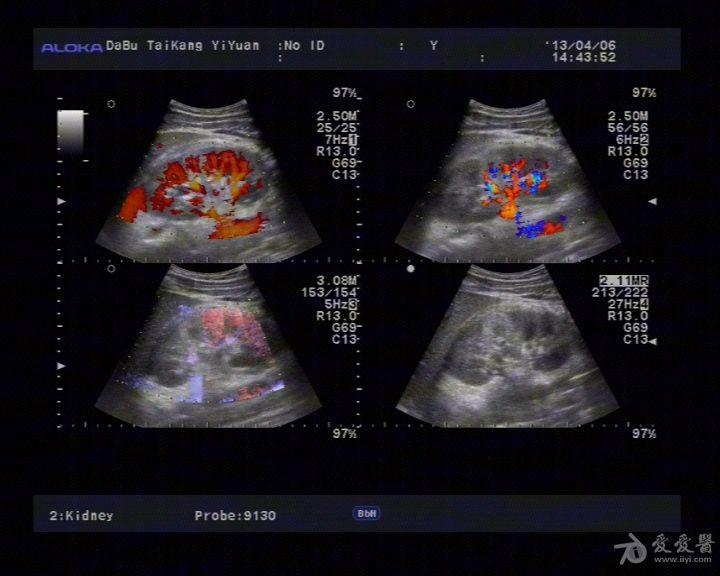

肾脏挫裂伤 - 超声医学讨论版 - 爱爱医医学论坛

图片尺寸768x576